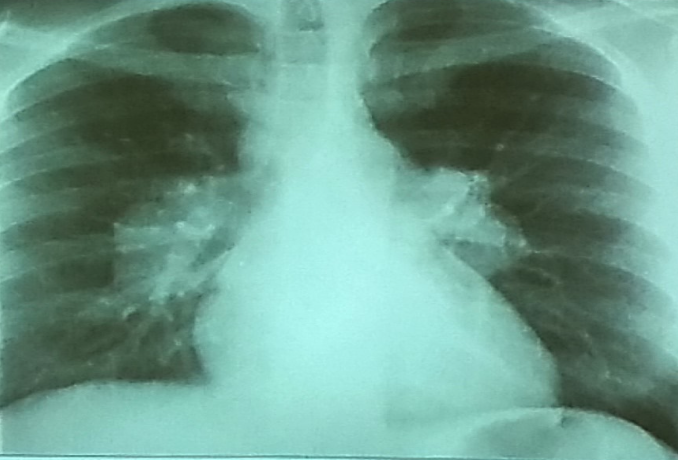

Case 17 Z

40 year old man presented with cough and shortness of breath for six months. Six weeks ago he noticed painful lumps on the skin of his legs which had resolved in two weeks

What is the abnormality in CXR? Hilar lymphadenopathy (enlarged lymph nodes in the hila of both lungs)

-

What is the most likely diagnosis? Sarcoidosis; lump

Bilateral Hilar Lymphadenopathy: Causes

| Category | Causes |

|---|---|

| Sarcoidosis | Sarcoidosis |

| Infection | * Tuberculosis * Fungal infection * Mycoplasma * Intestinal Lipodystrophy (Whipple’s disease) |

| Malignancy | * Lymphoma * Carcinoma * Mediastinal tumors |

| Inorganic dust disease | * Silicosis * Berylliosis |

| Extrinsic allergic alveolitis | * Such as bird fancier’s lung |

| Less Common Causes | * Churg-Strauss syndrome * Human immunodeficiency virus * Extrinsic allergic alveolitis * Adult-onset Still’s disease |